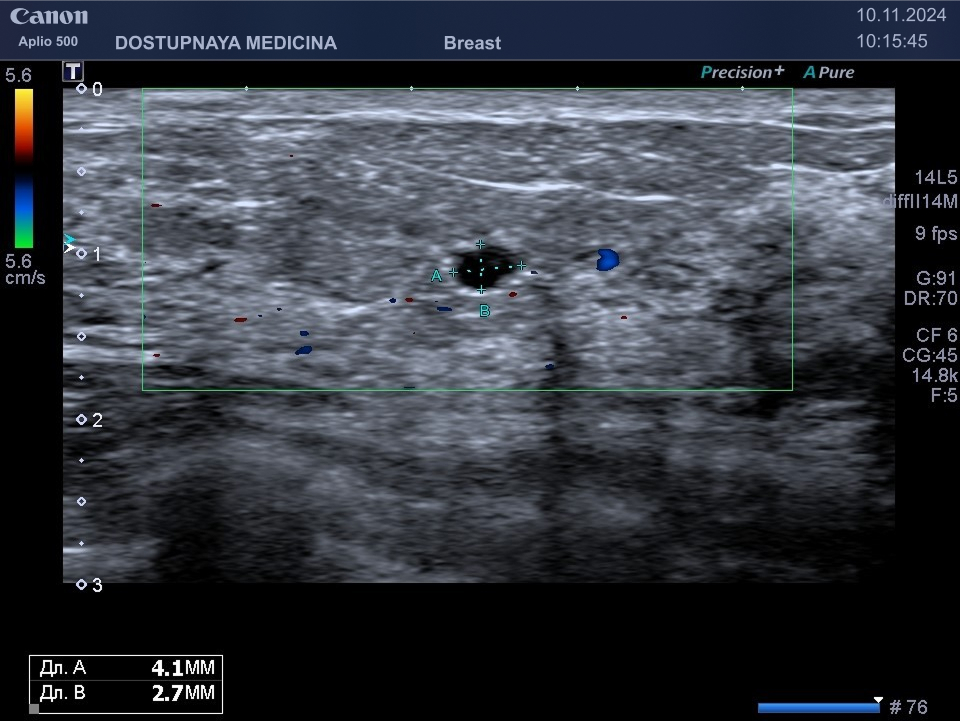

Киста может быть заполнена жидким или густым секретом. Киста с жидким секретом на УЗИ выглядит как анэхогенное (чёрное) образование округлой или овальной формы, киста с густым секретом на УЗИ выглядит как гипоэхогенное (серое) образование.

Кисты могут воспаляться, тогда при ультразвуковом исследовании в режиме ЦДК вокруг кисты отмечается усиление кровотока, пациентка при этом жалуется обычно на уплотнение и боль в области кисты молочной железы. Воспаление кисты может привести к её абсцедированию.

При ультразвуковом исследовании в кисте может быть визуализирован папиллярный компонент с кровотоком в режиме ЦДК. Так могут выглядеть цистаденопапилломы, которые считаются аблигатным предраком.